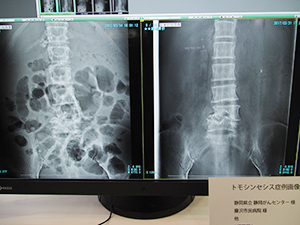

●「BENEO-Fx」のトモシンセシス撮影の臨床例を画像で紹介

一般撮影コーナーでは,トモシンセシス機能やエネルギーサブトラクション撮影機能などを搭載したデジタルX線画像診断システム「FUJIFILM DR BENEO-Fx」,ロングサイズパネル「CALNEO GL」と電動式立臥位撮影台「FM-PL1」を組み合わせた長尺撮影システムなどを展示した。

BENEO-Fxのトモシンセシス機能では,振り角は30°(15°×2),撮影時間は8秒で40枚の撮影を行う。再構成によって断層画像を生成してボリュームで観察できる。通常の一般撮影に連続して撮影でき,臥位だけでなく立位での撮影も可能で,低被ばくで患者の負担も少なく新たな診断情報が得られることが期待される。BENEO-Fxのコーナーでは,トモシンセシスの症例画像として“仙骨不顕性骨折(骨粗鬆症による脆弱性骨折)”“腰椎骨折”“播種による癌性胸膜炎”などの画像を提示し胸腹部領域でのトモシンセシスの有用性を紹介した。

トモシンセシスの症例画像:仙骨不顕性骨折 |

トモシンセシスの症例画像:腰椎骨折 |